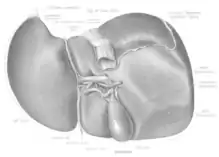

The liver is a dark reddish brown, wedge-shaped organ with two lobes of unequal size and shape. A human liver normally weighs approximately 1.5 kilograms (3.3 pounds)[9] and has a width of about 15 centimetres (6 inches).[10] There is considerable size variation between individuals, with the standard reference range for men being 970–1,860 grams (2.14–4.10 lb)[11] and for women 600–1,770 g (1.32–3.90 lb).[12] It is both the heaviest internal organ and the largest gland in the human body. It is located in the right upper quadrant of the abdominal cavity, resting just below the diaphragm, to the right of the stomach, and overlying the gallbladder.[5]

The liver is grossly divided into two parts when viewed from above – a right and a left lobe – and four parts when viewed from below (left, right, caudate, and quadrate lobes).[14]

The falciform ligament makes a superficial division of the liver into a left and right lobe. From below, the two additional lobes are located between the right and left lobes, one in front of the other. A line can be imagined running from the left of the vena cava and all the way forward to divide the liver and gallbladder into two halves.[15] This line is called Cantlie's line.[16]

Other anatomical landmarks include the ligamentum venosum and the round ligament of the liver, which further divide the left side of the liver in two sections. An important anatomical landmark, the porta hepatis, divides this left portion into four segments, which can be numbered starting at the caudate lobe as I in an anticlockwise manner. From this parietal view, seven segments can be seen, because the eighth segment is only visible in the visceral view.[17]